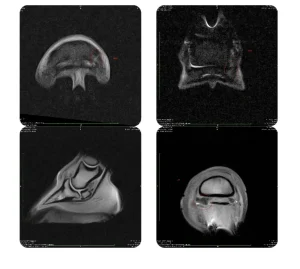

- Other advanced tests, such as scintigraphy and magnetic resonance imaging, in collaboration with specialised equine veterinary hospitals.